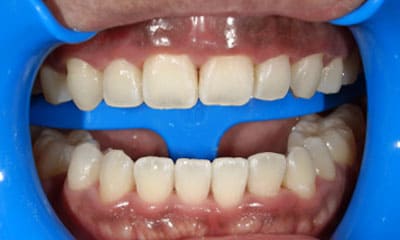

● C4を超え歯根までの虫歯を抜歯、スペースを利用して歯並び全体を整えた症例

藤沢デンタルオフィスの虫歯や破折で抜歯後の部分矯正